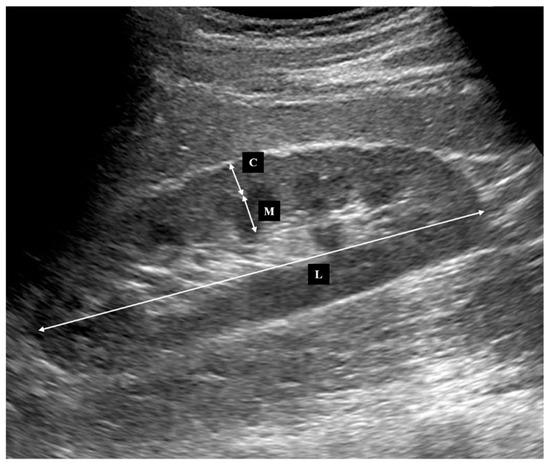

2.2. Ultrasonography